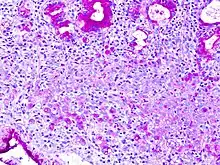

In histology, a signet ring cell is a cell with a large vacuole. The malignant type is seen predominantly in carcinomas.

The name of the cell comes from its appearance; signet ring cells resemble signet rings. They contain a large amount of mucin, which pushes the nucleus to the cell periphery. The pool of mucin in a signet ring cell mimics the appearance of a finger hole and the nucleus mimics the appearance of the face of the ring in profile.

A significant number of signet ring cells, generally, are associated with a worse prognosis.[6][7]